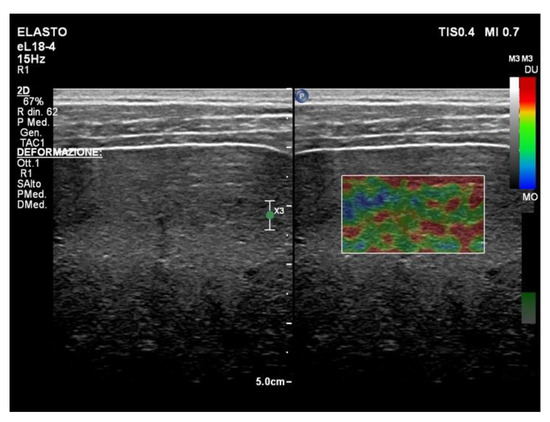

6. Liver Ultrasound Elastography in NAFLD Patients: Strain Elastography